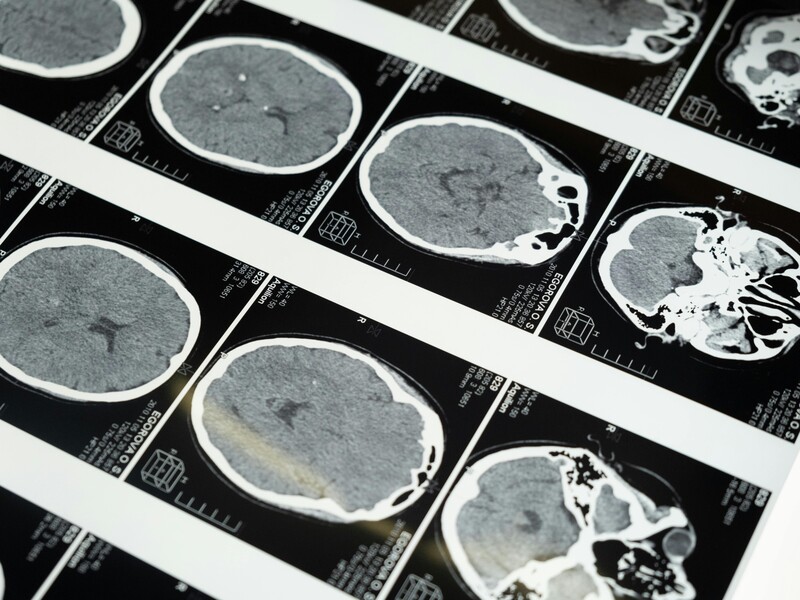

In modern medical imaging, radiation protection for healthcare staff is as critical as patient safety. While full-body aprons protect the torso and vital organs, the eyes remain highly susceptible to scatter radiation. Radiation-induced cataracts are a recognized occupational hazard, particularly for staff performing fluoroscopy, interventional radiology, and long-duration X-ray procedures.

Scatter radiation occurs when X-rays interact with the patient’s body or surrounding objects and change direction. Although lower in intensity than the primary beam, scatter radiation can reach sensitive areas such as the eyes, thyroid, and hands.

• Eyes are particularly vulnerable because the lens is sensitive to ionizing radiation, which can accumulate over time.

• Occupational exposure limits for the lens of the eye are 20 mSv per year according to the International Commission on Radiological Protection (ICRP).

Proper eye protection helps prevent radiation-induced cataracts and long-term vision impairment.